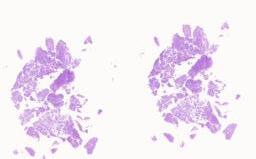

临床资料: 病人信息,女,69岁,取材部位:腋窝淋巴结临床病史:左侧腋窝下肿物7月余;特殊影像学及实验室检查:浅表超声:左侧腋窝肿大淋巴结。给予抗感染治疗(具体不详),自觉左侧腋窝淋巴结缩小。后患者自觉左侧腋窝肿物仍存在,再次就诊。胸部CT:1.左侧腋窝打发结节及团块影,请结合临床,建议CT增强检查:2.双肺散在磨玻璃结节影,多考虑炎性可能,建议随访观察;3.右肺上叶少许沿淋巴道分布条带状及结节状密度增高影,考虑淋巴来源病变,建议进一步检查实验室检查结果回示:血常规无异常。